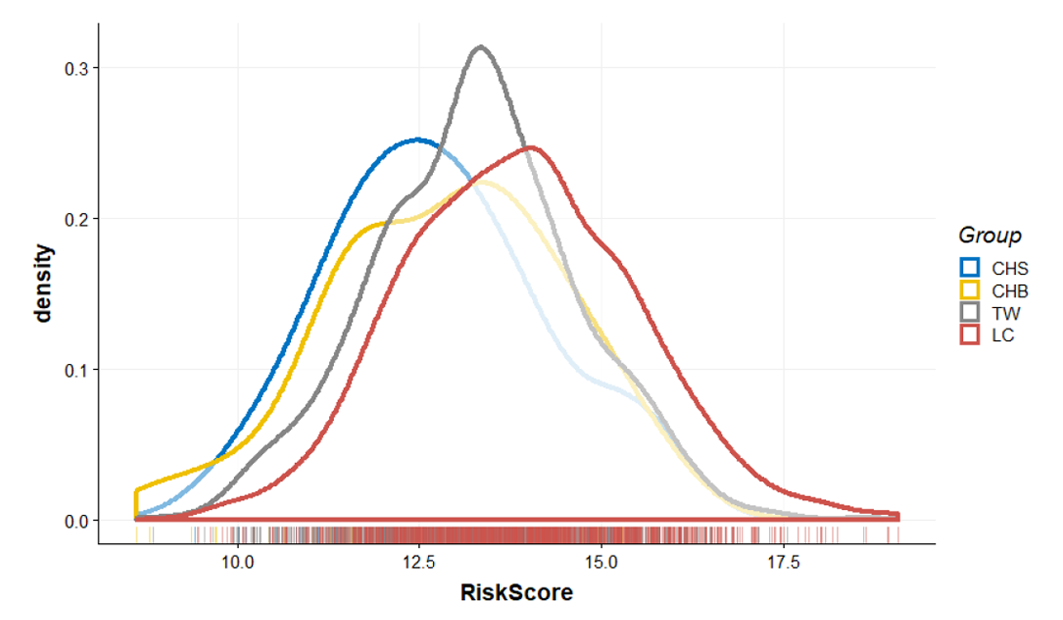

- Thông qua cơ sở dữ liệu công khai và tiên tiến, chúng tôi đã tổng hợp tất cả các vị trí đa hình nucleotide đơn (SNP) liên quan đến ung thư phổi và tạo ra một mô hình dự đoán rủi ro duy nhất. Chúng tôi không chỉ sử dụng thông tin bộ gen của những người khỏe mạnh trong cơ sở dữ liệu như Dự án 1000 gen và Ngân hàng sinh học Đài Loan, mà còn kết hợp nó với dữ liệu bộ gen quý giá của bệnh nhân ung thư phổi để đảm bảo rằng mô hình của chúng tôi có thể phản ánh một cách chính xác mức phân phối rủi ro ung thư phổi trong dân số.